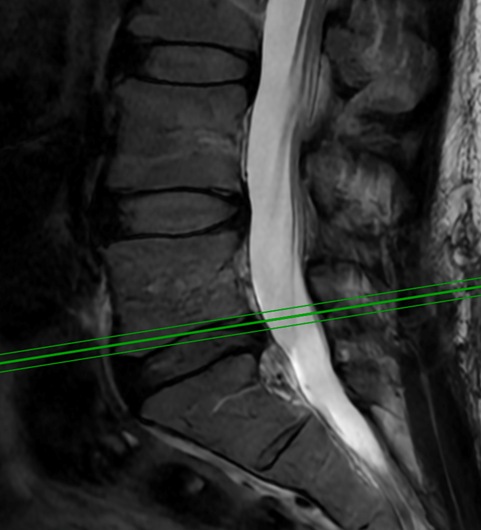

July 21, 2022

This 62-year-old female presents with chronic intractable low back pain with radiation down the front of her thighs. The patient had had two prior fusion surgeries: […]